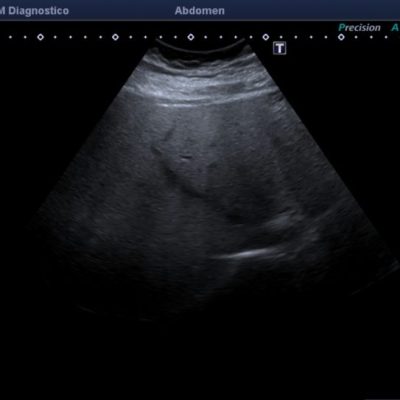

El médico de referencia le indica nueva ecografía de control, donde se observan múltiples y extensas lesiones focales hepáticas hiperecogénicas, redondeadas y confluentes, las cuales predominan en adyacencia a venas supra hepáticas, sin condicionar efecto de masa y sin alteración de la superficie hepática(fig. 1 y 2). Ante la valoración con Doppler color no presenta patrón de flujo peri ni intralesional y respeta el calibre de las venas supra hepáticas(fig. 3 y 4). Dada las características ecográficas se sospecha esteatosis focal multinodular confluente como principal diagnóstico presuntivo, siendo los diagnósticos diferenciales patologías de naturaleza infecciosa, tumoral o metastásica.